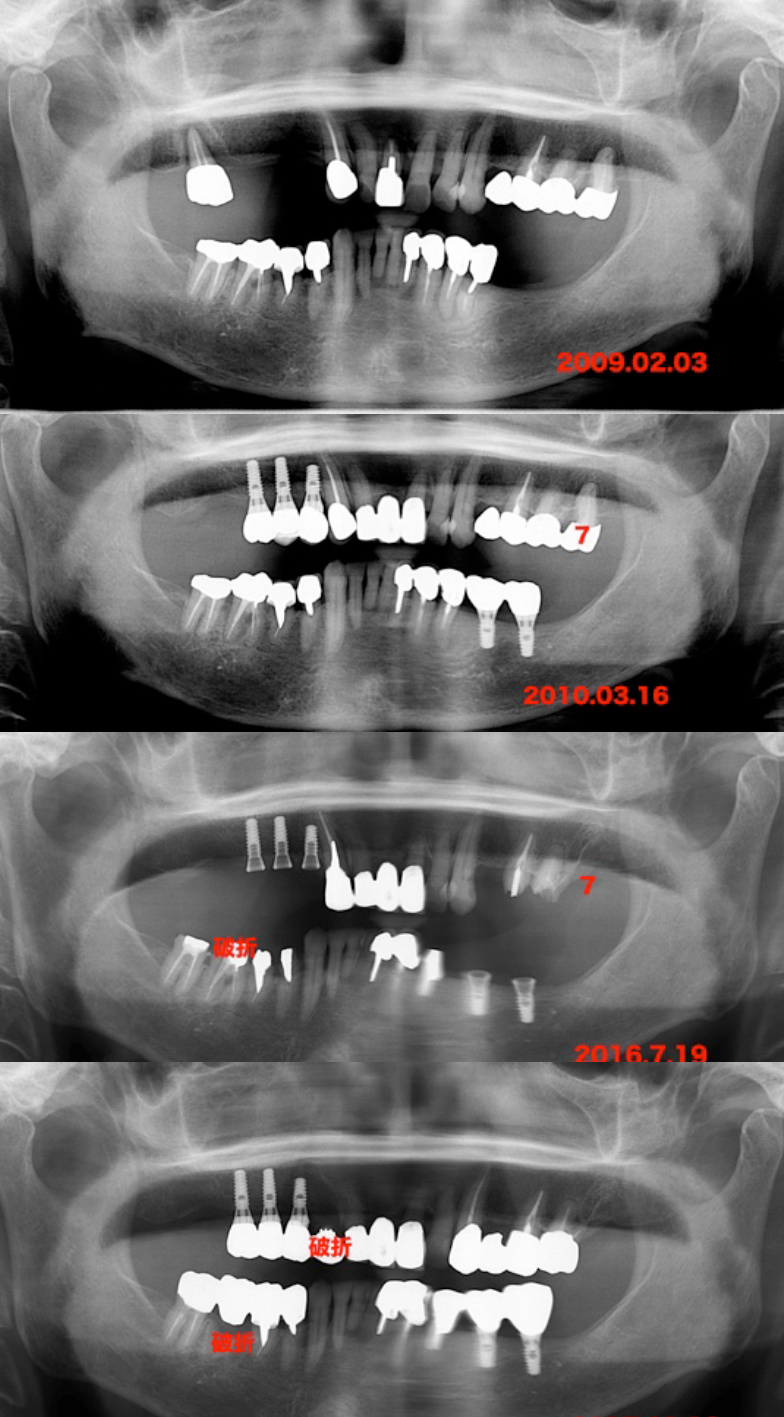

我々が結婚した当初何度か千葉に来た際に私が治療し

ました。しかし、右の写真の頃に奥歯がダメになり、

インプラントにすることにしました。たぶん80歳ぐ

らいの頃です。身体は非常に健康です。約1年ぐらい掛

けて右上と左下に計5本のインプラントを入れまし

た。その後、特に問題なく経過していましたが、左上

の7が虫歯になり、大分で抜歯をしました。どうやら

その頃から頭痛が出はじめたようです。久しぶりに

我々が見ると背中の曲がりが大きくなり、非常に無理

な姿勢に見えました。妹に聞いても気付いていません

でした。

2016.7.19のレントゲンで7の部位が無くなってい

て、右下が噛み割っていました。骨粗鬆症の薬を処方

されていたので、3ヶ月待って大分で抜歯をしてもら

いました。下の写真は仮歯に置き換えたところです。